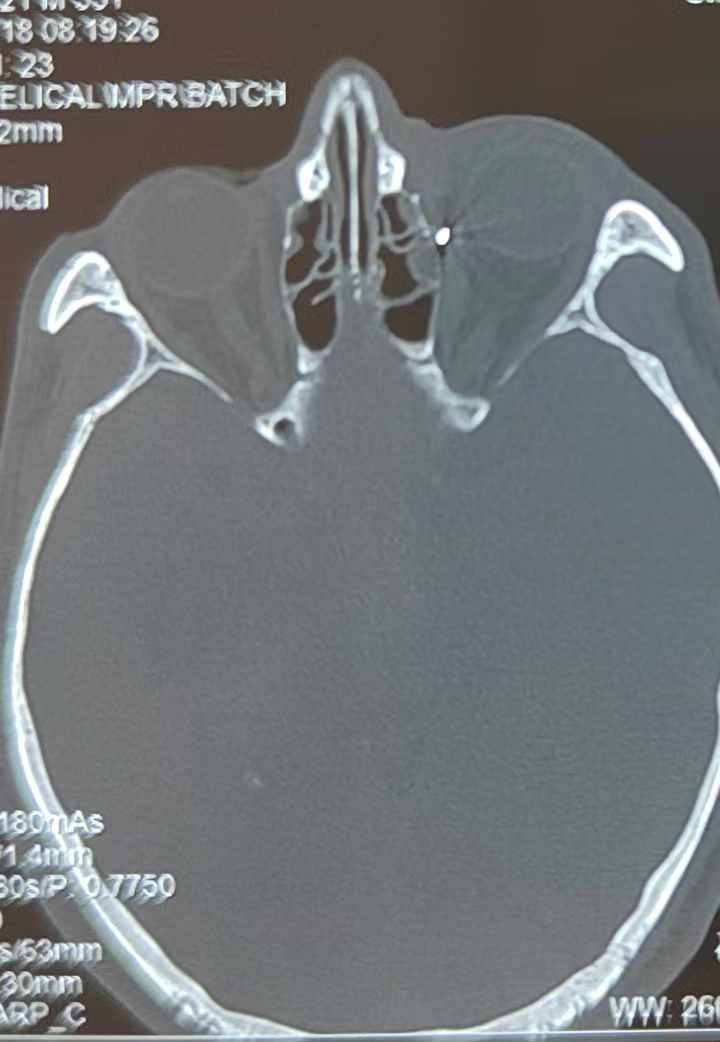

從CT報(bào)告中可以看出,高先生眼內(nèi)的異物不是很大,但位于眼窩深處,緊鄰鼻骨,從CT影像判斷應(yīng)該是金屬或合金異物。一般臨床上遇到這樣的情況,醫(yī)生會(huì)建議“保守觀察”,若異物傷及神經(jīng)、發(fā)生炎癥感染等,則需到條件較好、有眼眶病和眼外傷專業(yè)醫(yī)師的醫(yī)院進(jìn)行二期眶內(nèi)異物取出術(shù)(2021年《中國眼眶異物診斷和治療專家共識》)。

李海波博士介紹,眶內(nèi)異物想要通過手術(shù)取出,難度很大,一是因?yàn)槲恢秒[匿,無法實(shí)現(xiàn)可視化操作;二是如果是磁性異物,現(xiàn)有手術(shù)工具磁性強(qiáng)度有限,很難吸出這么深的異物;三是可操作空間極為狹小,眶周軟組織多,異物周邊包裹緊密,像高先生這種情況,異物周邊還有很多神經(jīng)、血管,手術(shù)難度更高。

手術(shù)十分順利,李海波博士設(shè)計(jì)好了取出路徑,用這根細(xì)磁棒取出了一個(gè)米粒大小的鐵屑,過程中未造成二次傷害和大創(chuàng)面?zhèn)?。術(shù)后CT檢查顯示,高先生眼內(nèi)再無異物,他此時(shí)才松了一口氣。